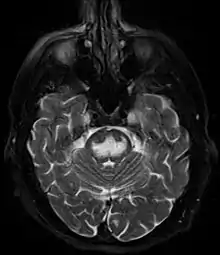

It can be diagnosed clinically in the appropriate context, but may be difficult to confirm radiologically using conventional imaging techniques. Changes are more prominent on MRI than on CT, but often take days or weeks after acute symptom onset to develop. Imaging by MRI typically demonstrates areas of hyperintensity on T2-weighted images.[29]